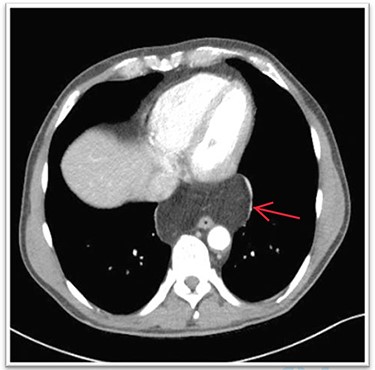

We restricted the intervention to an anatomical repair of the hiatal region. Fundoplication was not indicated because preoperative examination revealed no symptoms of reflux disease. The first three postoperative days were uneventful, and the patient responded well to puréed food. After receiving solid food on postoperative day four, the patient was regurgitating multiple times per day and complaining of globus sensation. A contrast-enhanced oesophagogram showed near-complete stenosis of the esophagogastric junction (Fig. 4). Gastroscopy was crucial to avoid an unnecessary surgical exploration as it showed the stenosis was not of mechanical origins such as a too tight hiatoplasty or fundoplication but was caused by a food bolus hindering optimal passage. The bolus was removed during gastroscopy and globus sensation disappeared thereafter. The remaining postoperative period was uneventful, with normal diet and no feelings of retrosternal pressure at hospital discharge.

The barium oesophagogram showing a near to total stenosis caused by alimentary bolus.